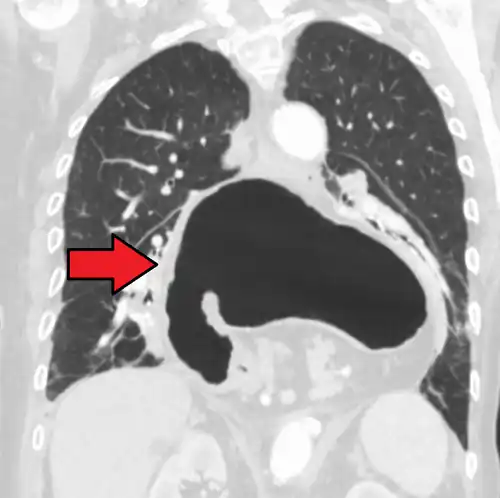

A hiatal hernia as seen on CT

A hiatal hernia as seen on CT -

A large hiatal hernia as seen on CT imaging

A large hiatal hernia as seen on CT imaging -

A large hiatal hernia as seen on CT imaging

A large hiatal hernia as seen on CT imaging -